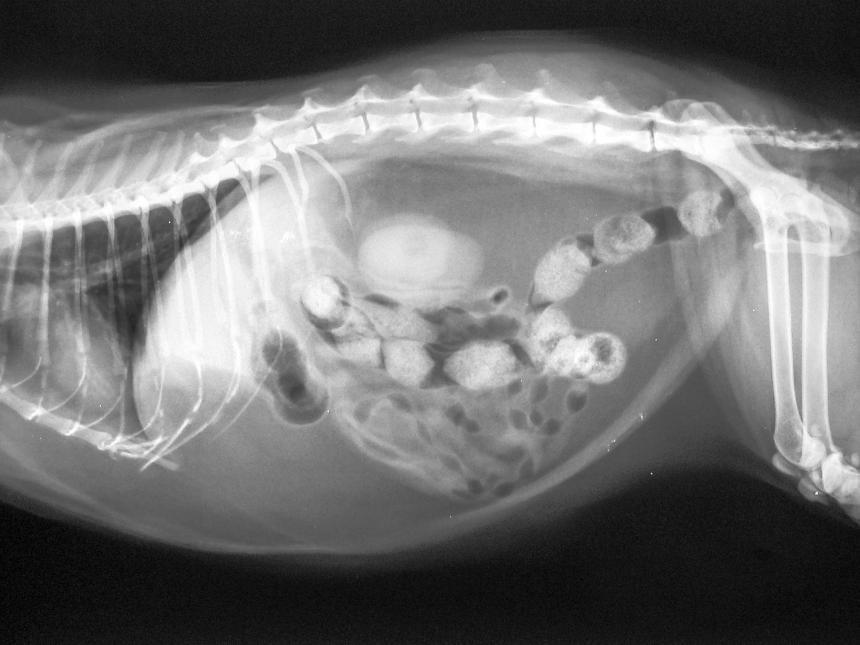

The cost of a x-ray will vary according to the doctors specialization and the type of x-ray used. Do tumors appear on X-rays of cats. These type of scans can detect broken bones dental problems gastric problems asthma heart disease and even pregnancy.

Rs 5000-Rs 2500-Avail Offer Now. This is much more difficult to accomplish with a dog than with a human. Radiographs X-rays offer vets a non-invasive way to look at what is happening on the inside of your pet.

Dental x-rays can range from 75 to 150 to x-ray all your cats teeth. Heceta Head Light is perched 205 feet above the Pacific Ocean on Oregons central coast. The two main types of tissues we look at using X-rays are bones and soft tissue structures.